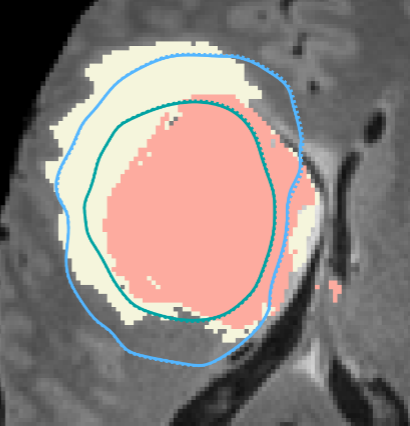

Figure from Murray Law in Pulmonary Arteries

Revisiting Murray's Law in Pulmonary Arteries: Exploring Branching Patterns and Principles

SA Correa, A Kachabi, M Colebank, CE Miles, N Chelser

J Biomech Eng 2025 PDF